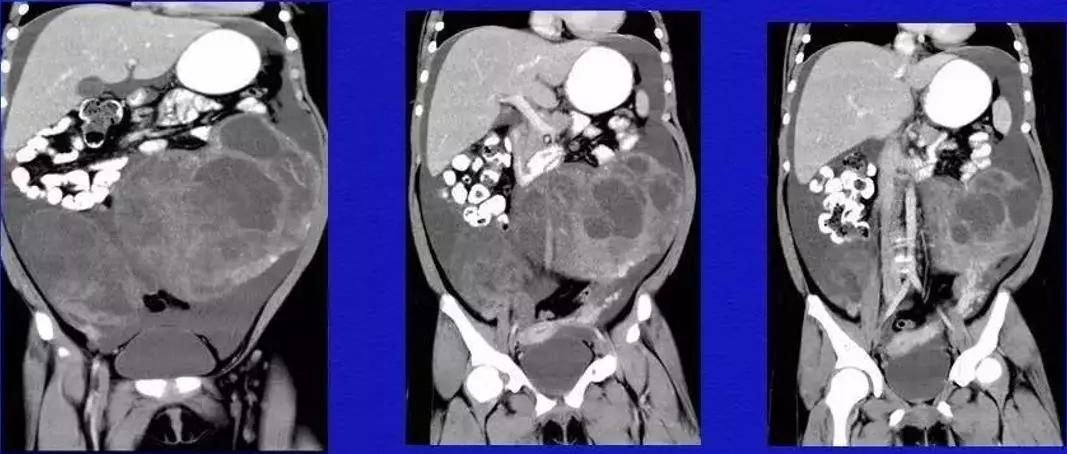

病例10

女,39 岁,体检发现盆腔肿块1月余

CA125:51U/ml

病理:左侧卵巢卵泡膜-纤维瘤